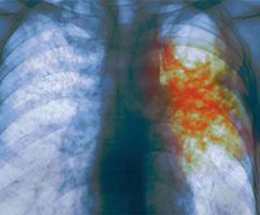

Տուբերկուլոզը բուժվող հիվանդություն է, Հայաստանում բուժումն անվճար է: Այս խոսքերով են ամեն անգամ ոլորտի մասնագետները դիմում բնակչությանը` հորդորելով երկարատև հազի, պարբերական քրտնարտադրության և հյուծվածության ախտանիշների դեպքում անպայման ստուգվել տարածքային պոլիկլինիկայում, որտեղ ախտորոշվելու համար կան բոլոր պայմանները: Տարածքային բժիշկները ևս վերապատրաստվել են հավուր պատշաճի բնակչությանը սպասարկելու համար:

Կազմակերպիչները ևս մեկ անգամ փաստեցին` ժամանակին չբուժվելու կամ բուժումը կիսատ թողնելու դեպքում`հիվանդը կանգնելու է մի շարք խնդիրների առջև, չբուժվելու պարագայում` ընդհուպ մահ կամ հաշմանդամություն, իսկ ընդհատելու դեպքում` դեղազգայուն տուբերկուլոզից անցում դեղակայուն տուբերկուլոզի կամ բազմակայուն տուբերկուլոզի, որոնց բուժումն անհամեմատ դժվար է:

Պարզաբանենք, որ դեղազգայուն տուբերկուլոզի դեպքում հիվանդության դեմ պայքարում են 4-5 դեղամիջոցներով` 6-8 ամսում, իսկ դեղակայուն տուբերկուլոզի դեպքում` բուժումն ընթանում է ավելի շատ դեղամիջոցներով և կողմանկի ազդեցություններով` 2 տարի, իսկ այն հիվանդների հետ, ովքեր հոգեպես պատրաստ չեն անցնելու այդ ճանապարհը, հոգեբան է աշխատում:

Նա տեղեկացրեց, որ տուբերկուլոզը Հայաստանում 2005 թ. հետո նվազման միտումներ է դրսևորում. 2011 թ. 9-ը ամիսների ընթացքում արձանագրվել է 1209 դեպք, 2010-ի` նույն ժամանակահատվածի 1329-ի դիմաց:

Նշենք, որ չբուժվելու դեպքում հիվանդը կարող է 1 տարվա ընթացքում վարակել 10-15 մարդու, որոնց 10 տոկոսը կյանքի հետագա տարիներին կարող է հիվանդանալ տուբերկուլոզով: